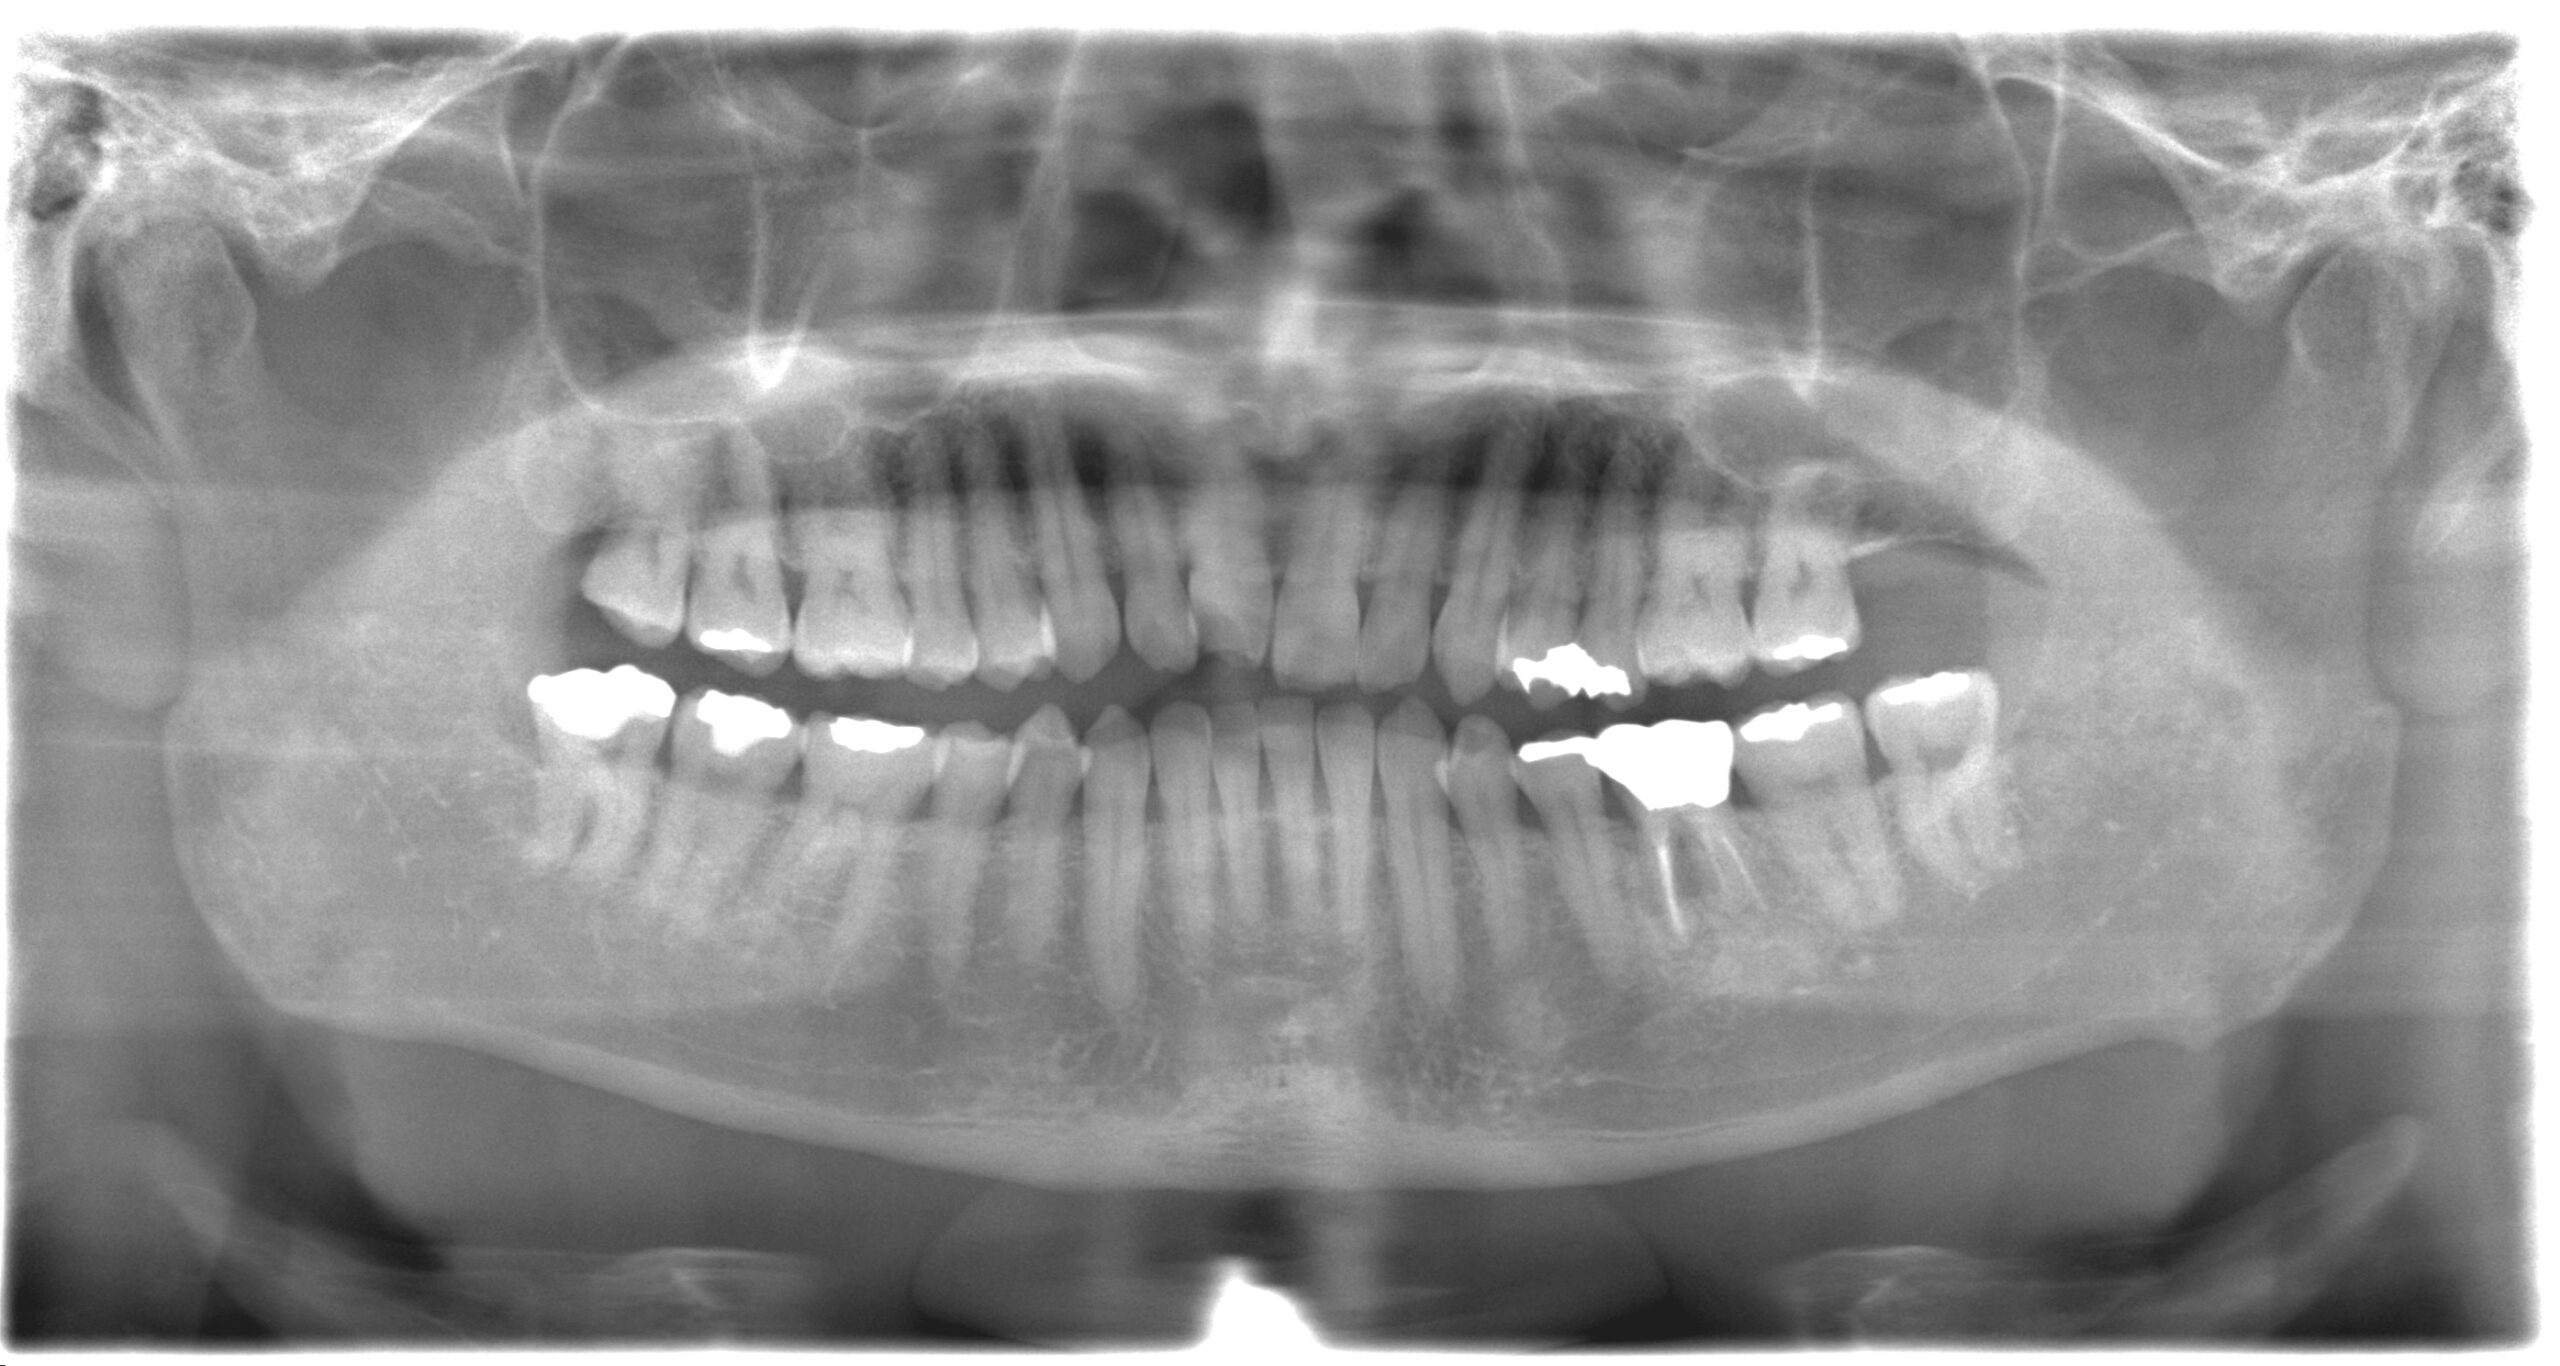

10数年前に左下奥歯の根管治療を行い問題なく過ごしていたが、急に噛むと痛みがある違和感が発生し、自宅近くの歯科医院を受診し抜歯を宣告されてしまった患者様(K・K様)【40代男性】

- パノラマレントゲン撮影

確かに根元が割れてしまっていて、抜歯が必要そうですね。